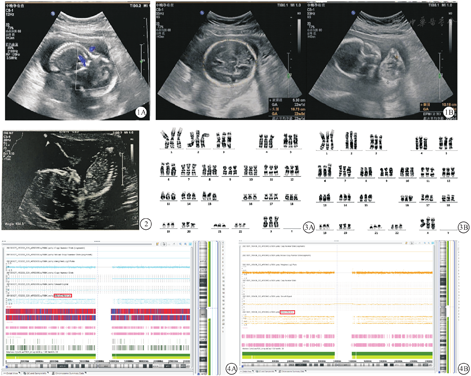

病例1 31岁,结婚2年。系第一胎,孕21周时超声检查发现胎儿测值小于孕周行产前诊断。平素月经规律,否认近亲结婚,否认家族遗传史,夫妻二人染色体核型正常。孕早期孕酮值正常,无先兆流产迹象。孕7周超声检查估孕龄符合。孕16+4周B超检查显示双顶径约29 mm符合15+2周,股骨长度约16 mm,符合14+6周;提示胎儿大小与孕周不符。孕17+周做进行无创产前检测(non-invasive prenatal testing,NIPT),结果未见明显异常。孕25周头围19.73 cm,腹围10.18 cm,腹围=1.94(参考值0.87~1.39,13~42w),提示为非匀称型胎儿生长受限(asymmetric fetal growth restriction, aFGR)(图1)。

病例2 32岁,流产1次,活产1次,现第3次怀孕,孕21周因超声检查胎儿测值小于孕周行产前诊断。平素月经规律,否认近亲结婚,否认家族遗传史,夫妻二人染色体核型正常。孕早期无腹痛,无阴道流血现象。孕16+4周超声检查显示双顶径34 mm符合16+4周,头围122 mm符合16+1周,腹围78 mm符合14+2周,股骨19 mm符合15+5周,胎儿右侧脑室宽约9 mm,左侧脑室宽约8 mm,胎儿下颌略后缩,FNMA角134.3°(参考值142°-151°),提示胎儿测值小于孕周伴不均衡,单脐动脉(图2)。

两例孕妇知情同意后均选择同时进行细胞遗传学检查和基因芯片检查。完善术前检查并签署知情同意书后,孕妇1与孕妇2分别于孕22周和孕21周在超声引导下行羊膜腔穿刺术,各取羊水30 mL,其中20 mL行细胞遗传学检查,10 mL行单核苷酸多态性微阵列分析(single nucleotide polymorphism array, SNP-array)。两例胎儿羊水细胞染色体核型均为69,XXX(图3)。两例胎儿羊水细胞SNP-array结果与核型一致,提示为三倍体(图4)。